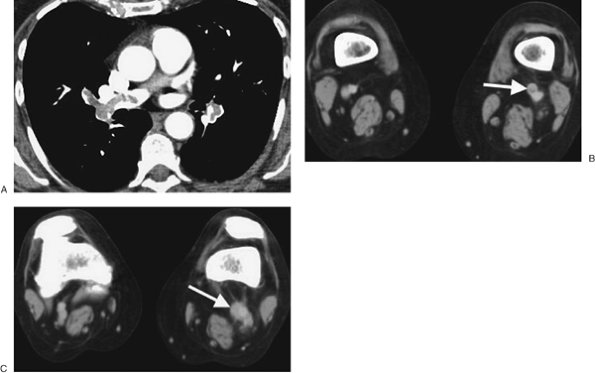

FIGURE 17-18. Deep venous thrombosis and acute PE. A: CTPA of a 66-year-old woman with an endometrial mass and left leg swelling shows bilateral PE. B: CTV performed immediately after the CTPA shows left DVT (arrow). C: CTV at a more inferior level shows expansion of the involved left lower-extremity vein and soft tissue stranding of the adjacent fat (arrow).

PE and DVT are different manifestations of the same clinical disease. One advantage of CTPA is the ability to add CTV, from the iliac crest to the tibial plateau, to detect DVT in the legs

and pelvis (Figs. 17-20 and 17-21). Both CTPA and CTV can be accomplished with the same bolus of contrast agent. Unlike lower-extremity ultrasound, CTV can image the external and internal iliac veins. Venous thrombosis can also occur in the upper extremities and in the thorax and can be detected on CTPA (Fig. 17-22).